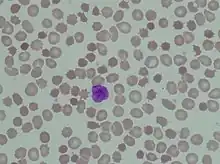

The signs and symptoms of abetalipoproteinemia appear in the first few months of life (because pancreatic lipase is not active in this period). They can include failure to gain weight and grow at the expected rate (failure to thrive); diarrhea; abnormal spiny red blood cells (acanthocytosis); and fatty, foul-smelling stools (steatorrhea).[9] The stool may contain large chunks of fat and/or blood. Infants often present with gastrointestinal problems caused by the poor fat absorption, which also contributes to steatorrhea. Other features of this disorder may develop later in childhood and often impair the function of the nervous system. They can include poor muscle coordination, difficulty with balance and movement (ataxia),[9][10] and progressive degeneration of the retina (the light-sensitive layer in the posterior eye) that can progress to near-blindness (due to deficiency of vitamin A, retinol).[9] Adults in their thirties or forties may have increasing difficulty with balance and walking. Many of the signs and symptoms of abetalipoproteinemia result from a severe vitamin deficiency, especially vitamin E deficiency, which typically results in eye problems with degeneration of the spinocerebellar and dorsal column tracts.

Acanthocytes are seen on blood smear.[17] Since there is no or little assimilation of chylomicrons, their levels in plasma remains low.